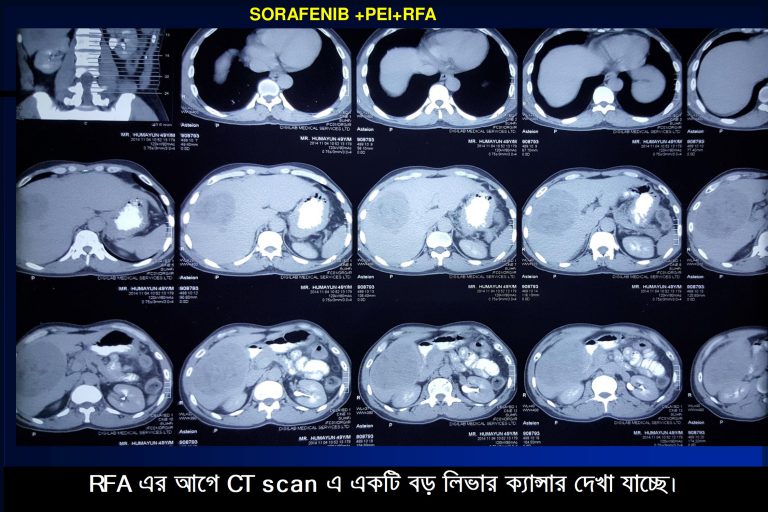

২। RFA (রেডিও ফ্রিকোয়েন্সি এব্লেশন)

১.TACE (ট্রান্স আরটারিয়াল কেমো এম্বালাইজশন)ঃ এই পদ্ধতিতে একটি বিশেষ ধরনের ক্যাথেটার দিয়ে রক্ত নালির মাধ্যমে লিভার টিউমারে প্রবেশ করে এক ধরনের বিশেষ বাহকের সাহায্যে সাধারন কেমোর চেয়ে প্রায় পঞ্চাশ গুন বেশি ঔষধ (কেমো) সরাসরি লিভারে প্রয়োগ করা হয় ও একই সাথে টিউমারে রক্ত প্রবাহ জেল ফোম (GEL Foam) এর মাধ্যমে বন্ধ করা হয়। এই চিকিৎসা পদ্ধতির মাধ্যমে বড় বড় টিউমারকে দুর্বল ও ছোট করে ফেলা সম্ভব হয়। এর কার্যকারীতার হার আনুমানিক ৬০%-৭০% এবং ১ থেকে ১.৫ বৎসর রোগী রোগ মুক্ত থাকে। বর্তমানে বড় টিউমার (8 cm এর চেয়ে বড়) ধবংস করতে TACE এর আগে অথবা পরে আর এফ এ অথবা মাইক্রোওয়েভ এব্লেশন পদ্ধতির সমন্বয় করে আরো উন্নত চিকিৎসা অত্যান্ত সফল ভাবে করা হচ্ছে। এর ফলাফলও খুবই উৎসাহ বাঞ্জাক। প্রায় ৮০%-৯০% রোগীর ক্যান্সার সম্পূর্ন ধ্বংস হয়ে যায়। এদের অধিকাংশ রোগী অনেক বৎসর সুস্থ্য থাকে।

২.RFA (রেডিও ফ্রিকোয়েন্সি এব্লেশন)ঃ এই পদ্ধতি ব্যবহারের মাধ্যমে ৫-৬ সেঃমিঃ লিভার টিউমার কে সম্পূন ধ্বংস করা সম্ভন হয় অথচ আশেপাশের সুস্থ কোষের কোন ক্ষতি হয় না। এ পদ্ধতির সফলতার হার ৮৫%-৯৫%। এ কারনে ৫-৬ সেঃমিঃ লিভার ক্যান্সার এর চিকিৎসা হিসেবে সারা বিশ্বে আর এফ এ (RFA) সব চেয়ে বেশি সমাদূত। এর পার্শ্ব প্রতিক্রিয়াও খুবই কম।